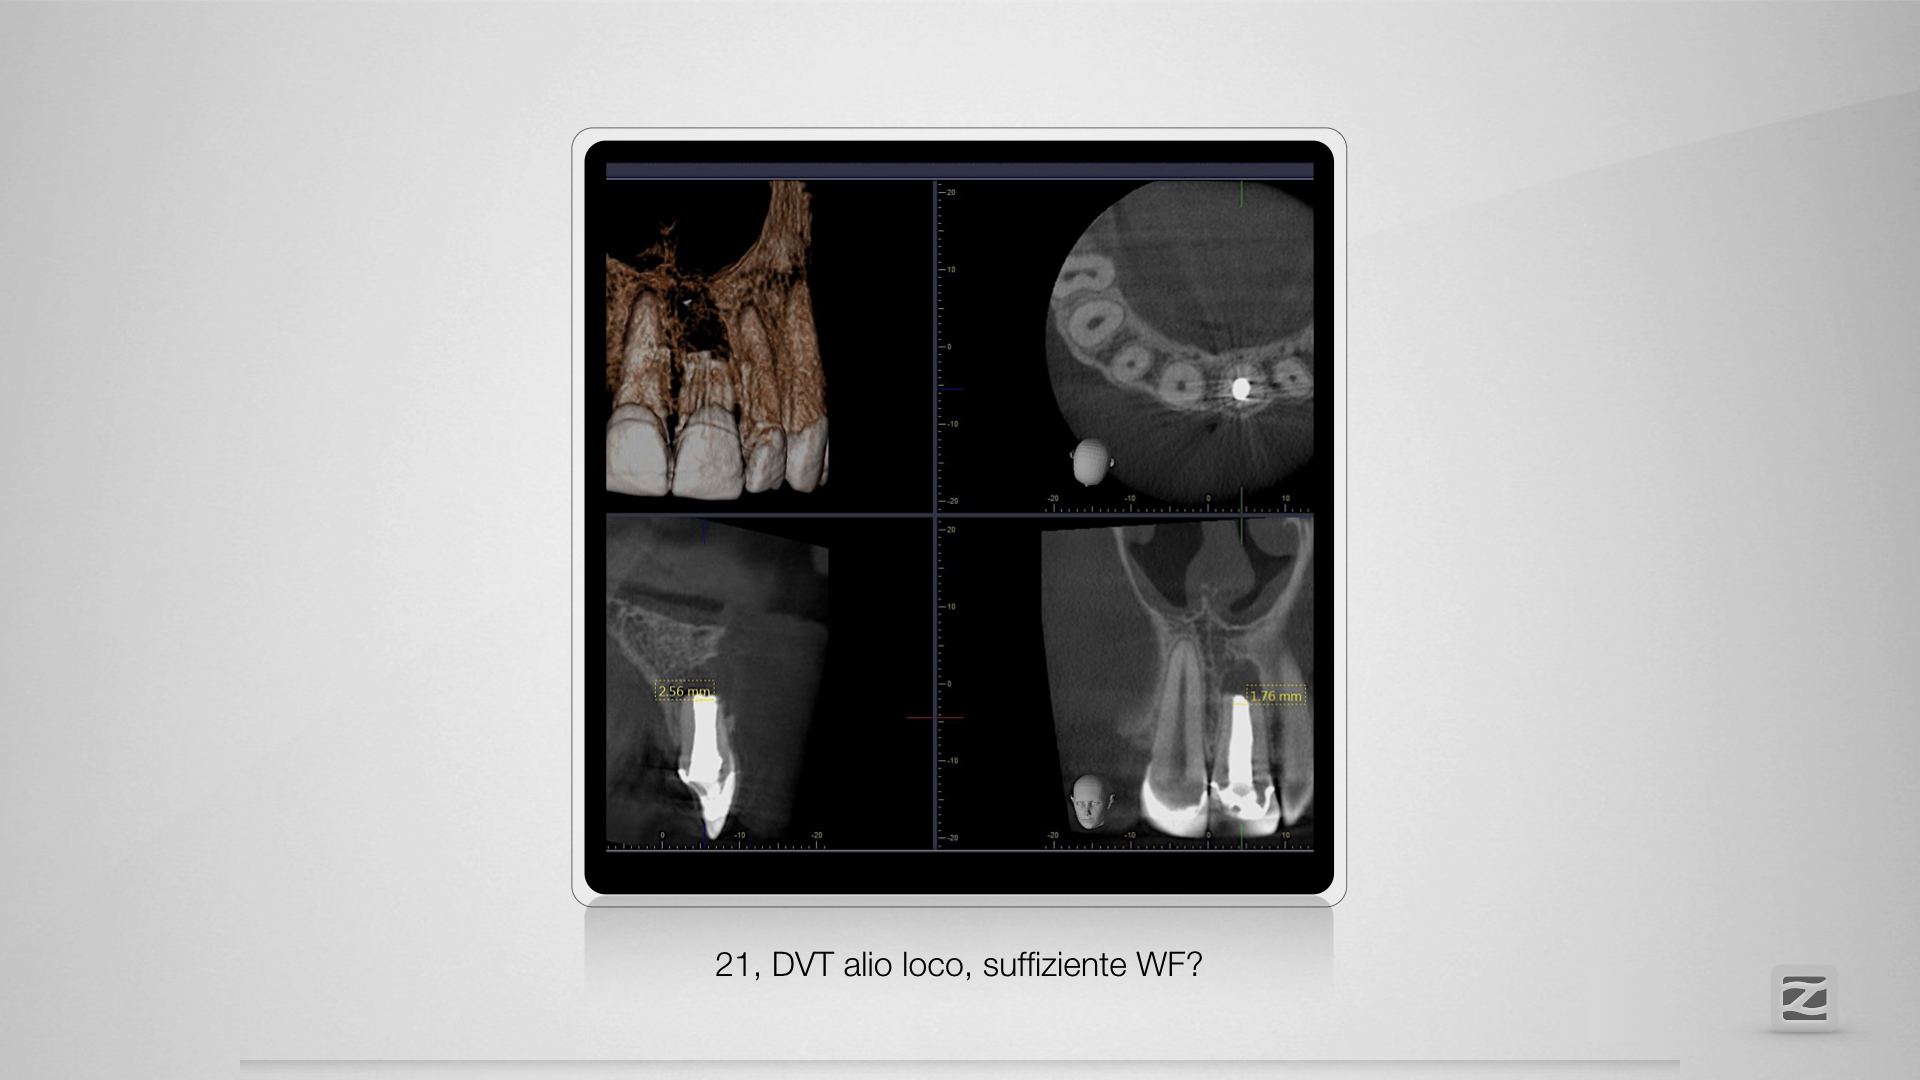

Der Schein trog!